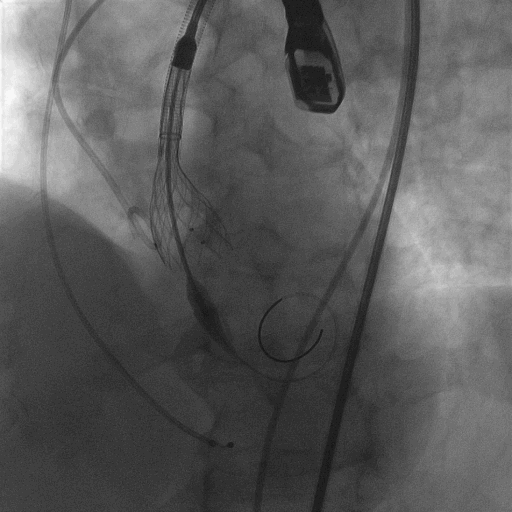

术中造影

18mm球囊预扩,有腰无漏

L23超高位释放

释放到2/3,观察瓣膜位置,与FEops评估一致,瓣膜发生了下滑

使用VenusA-Plus®回收功能以后,调整投射角度继续以高位释放

再次释放到2/3,造影观察瓣膜位置良好,选择全部释放

L23高位释放成功